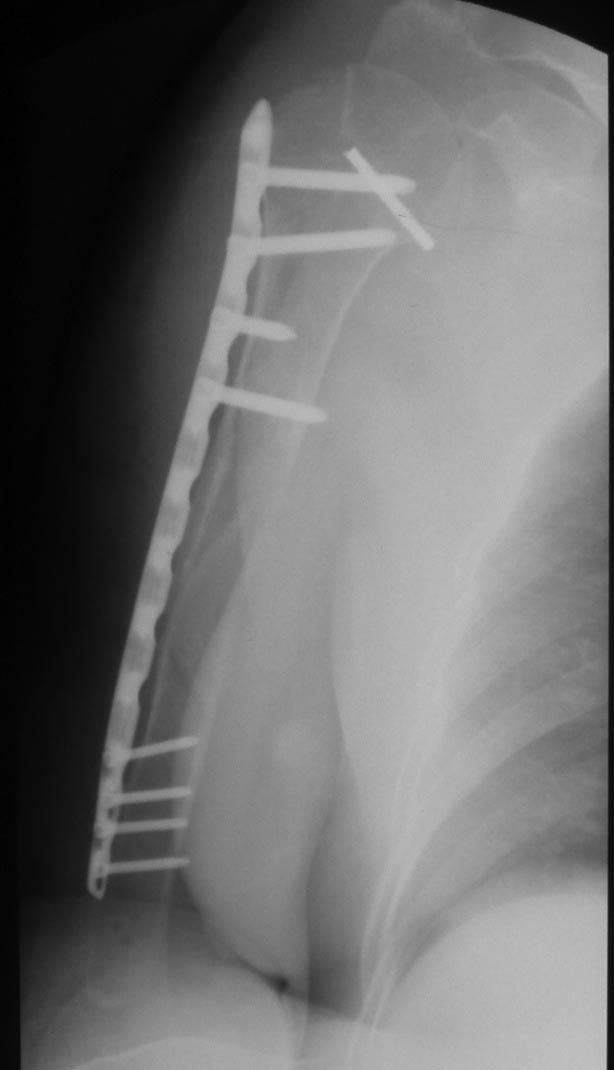

Как бы автор вопроса не убеждал себя, что в ситуации с гвоздем (его длиной, расположением относительно манжеты и бугорков и т.д.) все ясно, при таком качестве представленных рентгенограмм в единственной проекции никакой ясности быть не может.

В качестве примера - случай, который оперировал всего 2 недели назад, после похожего остеосинтеза, выполненного год назад. Пациентке 75 лет, тяжелый РА, легла для решения вопроса о ревизии тазобедренного сустава и заодно пожаловалась на то, что рука "крутиться" сама по себе, не поднимается. И болит, конечно. И посмотрите на разницу в информации на снимках головки плеча в двух противоположных проекциях. Даже комментировать ничего не нужно.